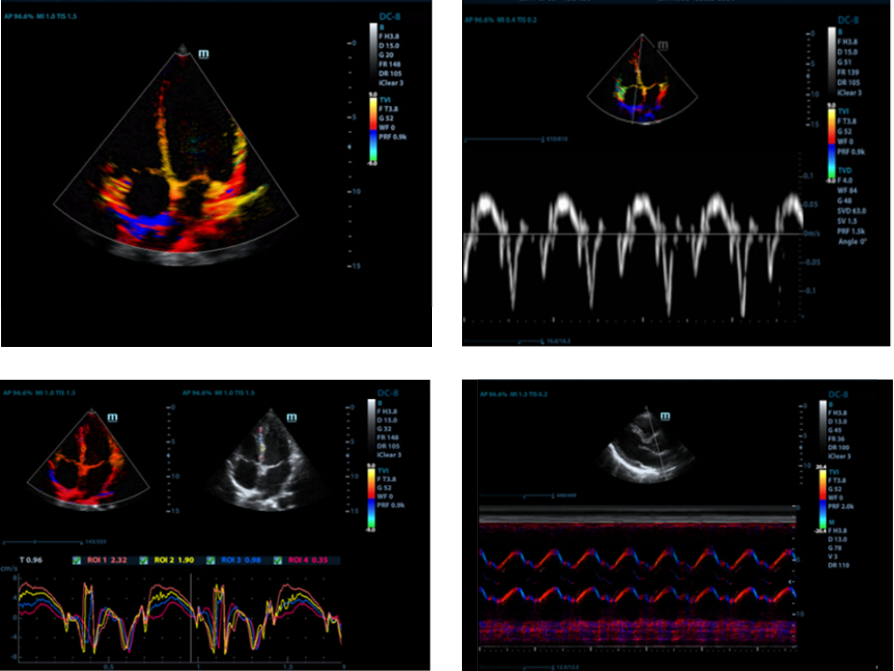

Free Xros CM?

Secara akurat menilai gerakan miokardial pada berbagai tahapan, dan sekaligus menentukan sinkronisasi miokardial. Laju bingkai yang tinggi memberi Anda hasil yang akurat:

TDI

Tissue Doppler Imaging memungkinkan Anda secara kuantitatif menilai fungsi dan gerakan miokardial lokal, sehingga memberikan mode TDI lengkap agar diagnosis lebih cepat dan langsung.

LVO dengan Ekokardiografi Stres

Kemampuan prima M9 memungkinkan opasifikasi LV selama stres, yang memperbaiki diskriminasi antara jaringan miokardial dan peredaran darah, sehingga memberikan visualisasi lebih baik atas permukaan endokardial. Fitur Stress Echo pada M9 menyertakan paket lengkap untuk stres farmakologis dan gema stres pengujian. Paket ini didukung oleh sistem pelaporan yang fleksibel dan dapat dioptimalkan untuk kebutuhan individual.

AutoEF

Cara pintar menganalisis klip gema 2D untuk mengenali bingkai diastol/sistol dan output EDV/ESV/EF secara otomatis, dsb. yang dihasilkan oleh metode Simpson.